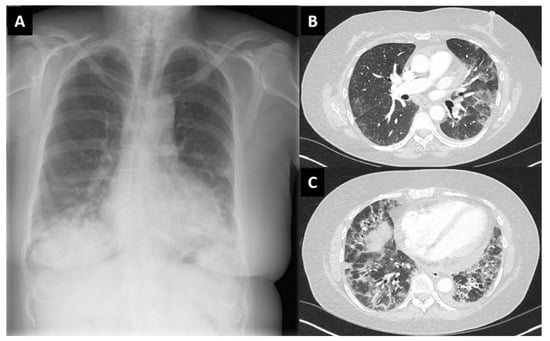

| Case 3 | No | AZD1222/ChAdOx1 | Amyopathic, sicca symptoms, shortness of breath. CRP 20 mg/L, CK normal. ANA + Myoblot + (SL 75, Ro52) | Heliotrope rash, mechanics hands. Interstitial lung disease. Pericardic effusion | Oral steroids, then IV cyclophosphamide followed by mycophenolate |

| York | dose 1, May 2021 | ||||

| Female, 58 | (4 weeks) | ||||